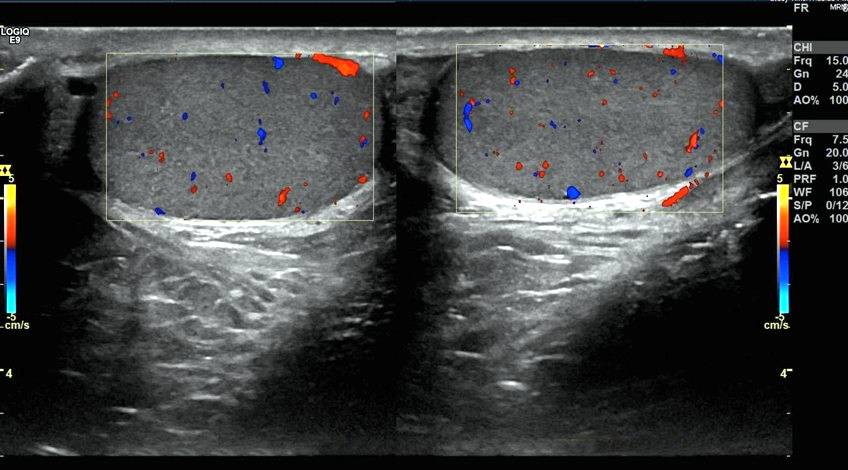

- Ecografía Partes Blandas (Estudio que se realiza en cualquier parte del cuerpo a nivel superficial).